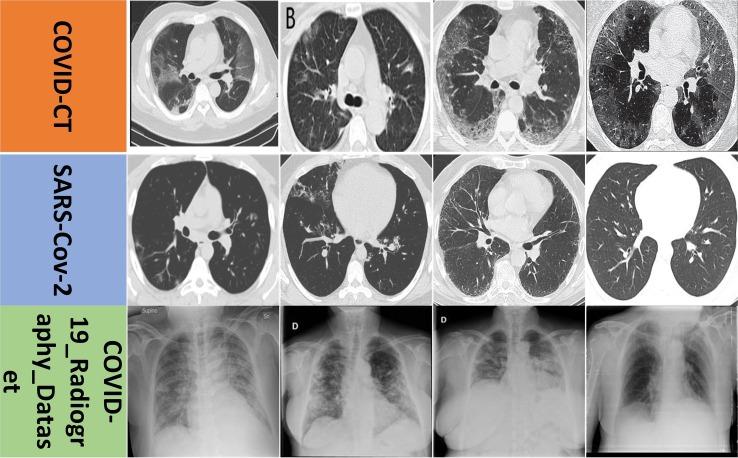

DCML:用于新冠肺炎识别的深度对比互学习

DCML: Deep contrastive mutual learning for COVID-19 recognition.

COVID-19 is a form of disease triggered by a new strain of coronavirus. Automatic COVID-19 recognition using computer-aided methods is beneficial for speeding up diagnosis efficiency. Current researches usually focus on a deeper or wider neural network for COVID-19 recognition. And the implicit contrastive relationship between different samples has not been fully explored. To address these problems, we propose a novel model, called deep contrastive mutual learning (DCML), to diagnose COVID-19 more effectively. A multi-way data augmentation strategy based on Fast AutoAugment (FAA) was employed to enrich the original training dataset, which helps reduce the risk of overfitting. Then, we incorporated the popular contrastive learning idea into the conventional deep mutual learning (DML) framework to mine the relationship between diverse samples and created more discriminative image features through a new adaptive model fusion method. Experimental results on three public datasets demonstrate that the DCML model outperforms other state-of-the-art baselines. More importantly, DCML is easier to reproduce and relatively efficient, strengthening its high practicality.

新型冠状病毒肺炎(COVID-19)是由一种新型冠状病毒引发的疾病形式。使用计算机辅助方法对COVID-19进行自动识别,有利于加快诊断效率。当前的研究通常聚焦于用于COVID-19识别的更深或更宽的神经网络。并且不同样本之间的隐含对比关系尚未得到充分探索。为了解决这些问题,我们提出了一种名为深度对比互学习(DCML)的新型模型,以更有效地诊断COVID-19。采用了基于快速自动增强(FAA)的多方式数据增强策略来丰富原始训练数据集,这有助于降低过拟合风险。然后,我们将流行的对比学习思想融入传统的深度互学习(DML)框架,以挖掘不同样本之间的关系,并通过一种新的自适应模型融合方法创建更具判别力的图像特征。在三个公共数据集上的实验结果表明,DCML模型优于其他现有最先进的基线模型。更重要的是,DCML更易于重现且相对高效,增强了其高实用性。